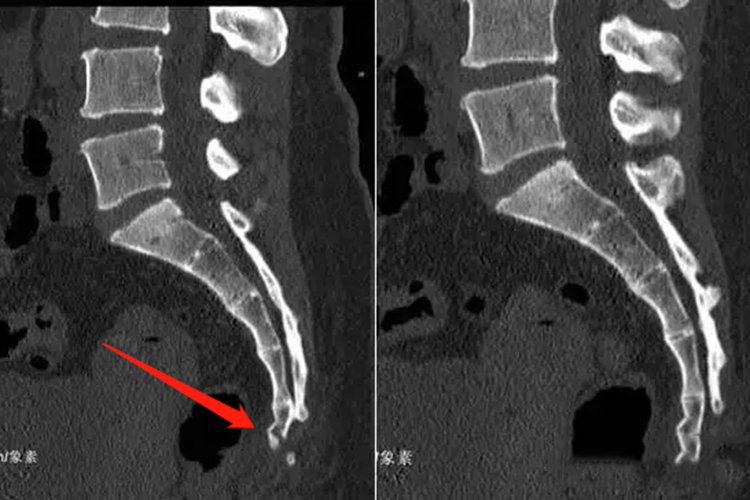

第5骶椎骨折一般是指骶骨尾段骨折,其位置在腰部中间偏靠下处,触摸时可有疼痛,有时可发现皮下瘀血,通常是由于摔倒所致。

人体共有5个骶椎,在第5个骶椎周围可触及第5骶椎下关节突形成的骶角,而第5骶椎骨折时通常是指骶骨尾段骨折,一般在腰部中间偏靠下的位置,可沿着骶角向内摸索触及到骨折部位,并可感觉到疼痛。

第五骶椎骨折若不存在神经损伤的情况,可以通过卧床休息保守治疗,若存在神经损伤,则需要进行手术治疗,遵医嘱行骶椎成形术。